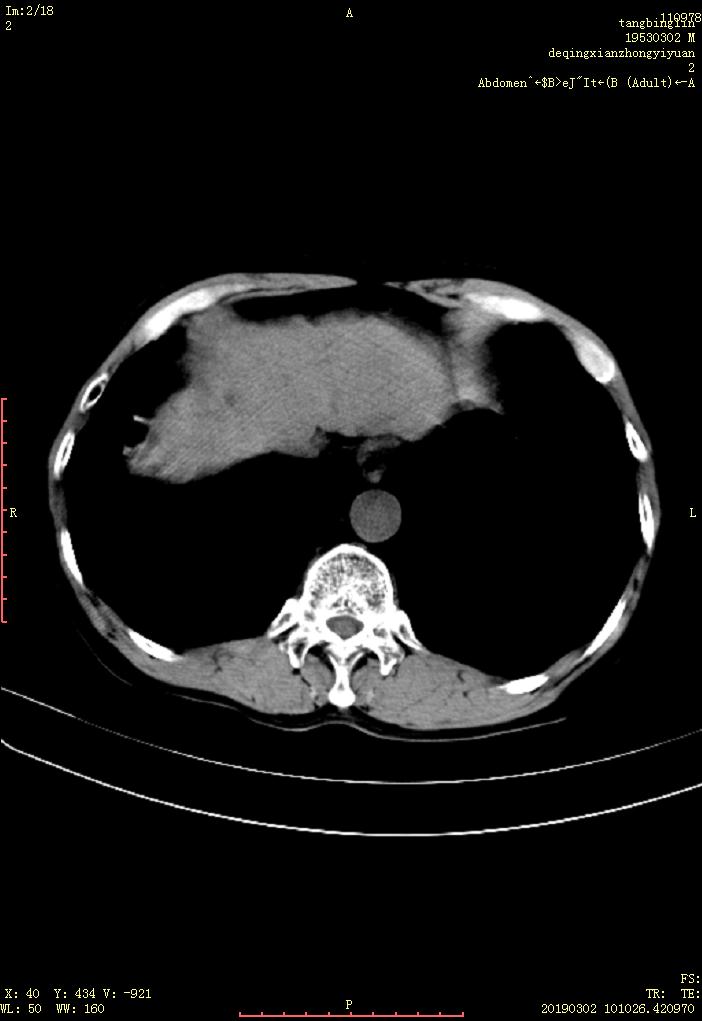

CT53514:男.66YB超提示肝脏多发性占位

男.66YB超提示肝脏多发性占位,外院5年前曾怀疑肝CA,延迟...请各位专家会诊一下。谢谢

肝右叶可见多各类圆型低密度影,边缘欠清晰,增强扫描明显强化,延迟呈低密度,考虑肝癌可能,转移瘤不除外

肝右叶可见多个稍低密度占位,边缘欠光整,部分病灶位于近肝包膜下。增强基本符合快进快出特点。考虑:肝内多发性占位---肝癌可能性大。

“快进快出”符合肝癌强化方式。